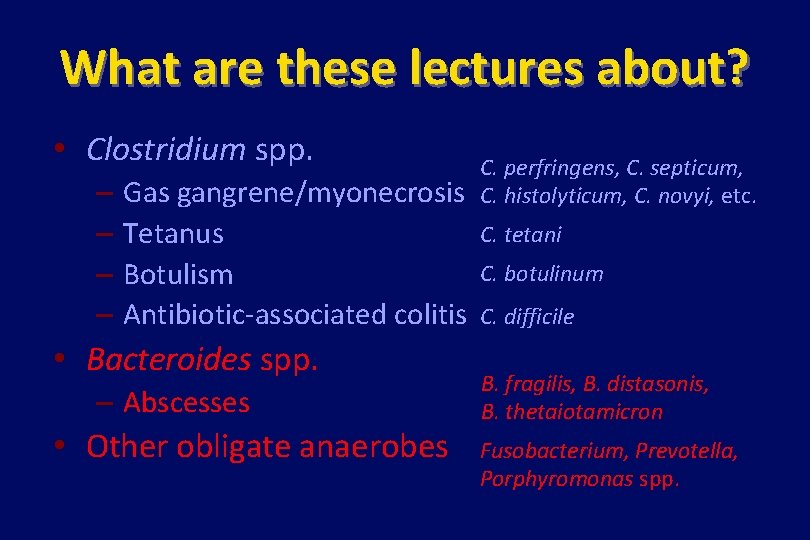

What are these lectures about? • Clostridium spp. – – Gas gangrene/myonecrosis Tetanus Botulism Antibiotic-associated colitis • Bacteroides spp. – Abscesses • Other obligate anaerobes C. perfringens, C. septicum, C. histolyticum, C. novyi, etc. C. tetani C. botulinum C. difficile B. fragilis, B. distasonis, B. thetaiotamicron Fusobacterium, Prevotella, Porphyromonas spp.